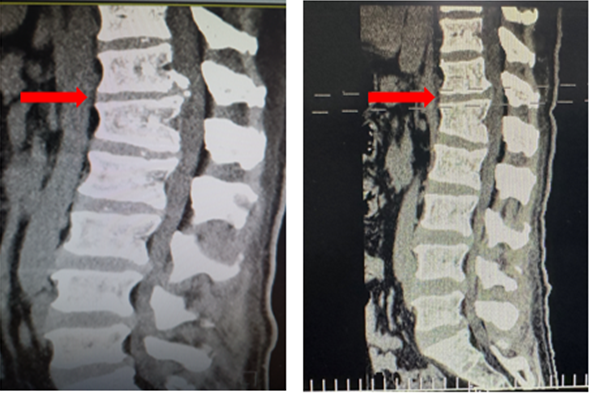

患者36岁,因肛周及会阴部胀痛麻木2年,加重1月入院。辗转多所医院,均建议采取传统外科开放手术治疗,患者因担心手术风险,迟迟不愿手术。经多方打听,患者慕名找到李全义主任医师,李全义主任医师接诊后,仔细研究患者的疾病特点,腰椎间盘突出症常见于低位椎间盘(L4/5、L5/S1),而该患者属于高位椎间盘突出(胸12/腰1节段),并且已经引起了马尾综合征,表现为会阴部及鞍区疼痛、麻木、二便障碍,高位椎间盘突出因高位椎管不如低位椎管容积大,在穿刺时容易损伤神经,造成严重并发症。与患者经过充分的沟通,决定采用目前骨科前沿技术-----机器人辅助微创手术。在病院主任刘时璋教授的带领下,李全义主任医师团队顺利为患者实施ORTHBOT脊柱机器人辅助椎间孔镜下胸12腰1髓核摘除、椎管扩大减压术,手术在局部麻醉下进行,以机器人辅助微创手术解除了患者的痛苦,减少手术创伤及并发症,缩短手术时间。

患者术前(左)及术后(右)影像学资料